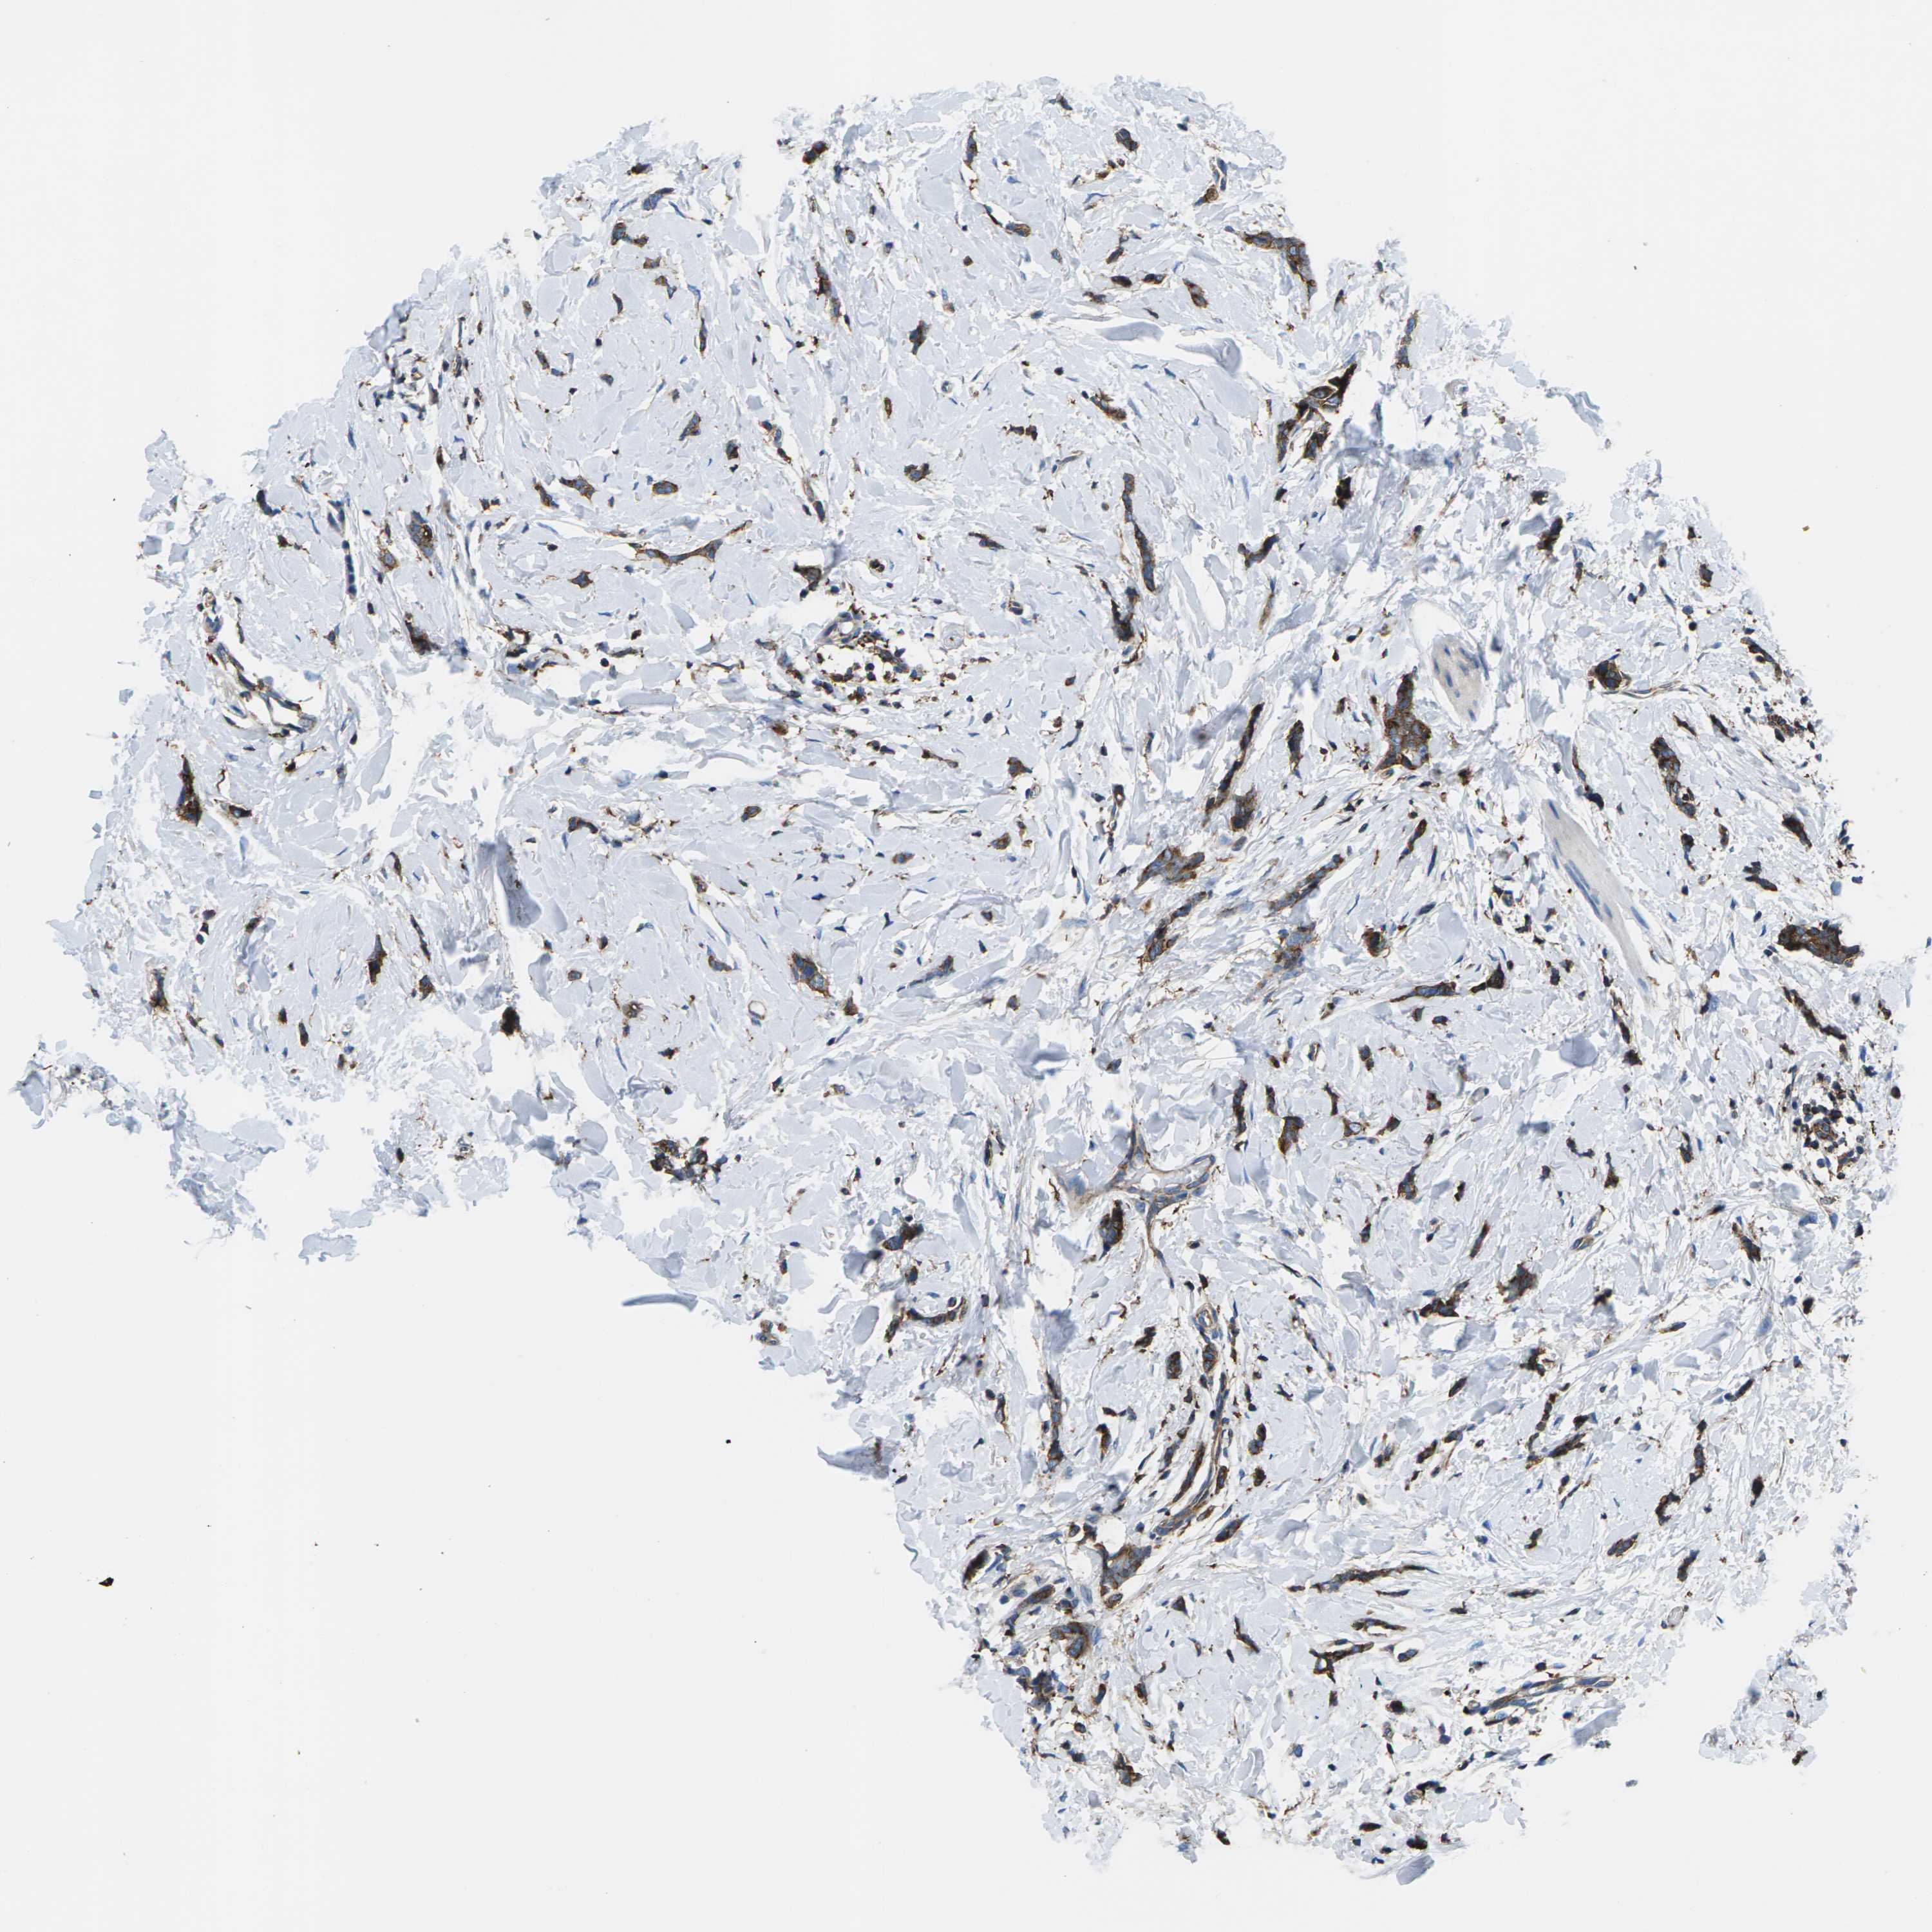

BRCA TCGA BRCA VALIDATION PROTEIN EXPRESSION